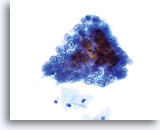

Glandulaire celclusters worden afgerond in PreservCyt-oplossing en kunnen uitschulpingen aan de randen van de groep vertonen. Let op de gladde, duidelijke cytoplasmische grenzen aan de rand van de groep.

40x